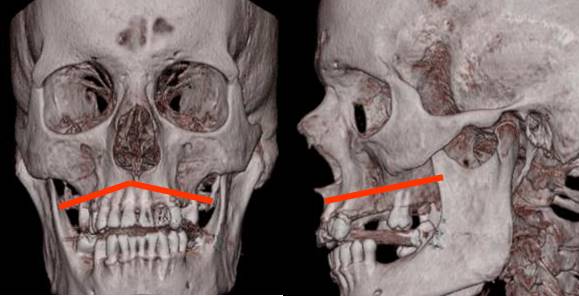

Fig 226. Lefort III.

A: TAC axial y B: TAC reconstrucción coronal. Múltiples fracturas en los antros maxilares y los rebordes orbitarios. En el lado derecho hay compromiso del piso de la órbita y el arco cigomático. (Flecha gruesa).

Fig 227. Lefort III.

A: Rx lateral, B: TAC axial y C: TAC reconstrucción coronal. Severo estallido facial con fracturas deprimidas de la parte anterior de la cara y Lefort III bilateral.